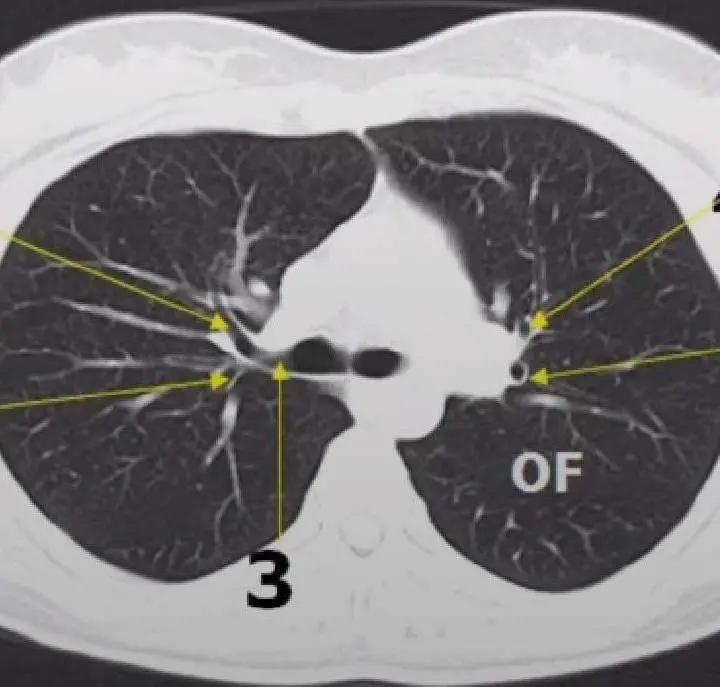

正常人的肺部CT,肺部纹理有序、清晰

老王的肺部CT显示:右侧胸腔多发肺大疱,已经造成呼吸衰竭,必须立即治疗!

从影像学检查来看

老王的肺部多发大疱

能有效呼吸的正常肺组织

已经极少